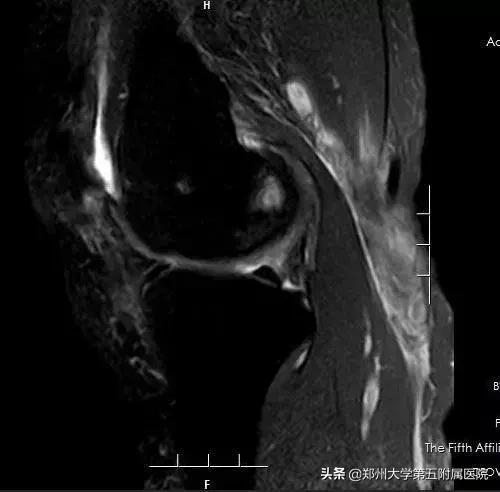

▲ 术后复查MRI囊肿明显缩小,随着囊壁的闭合,囊肿会逐渐消失